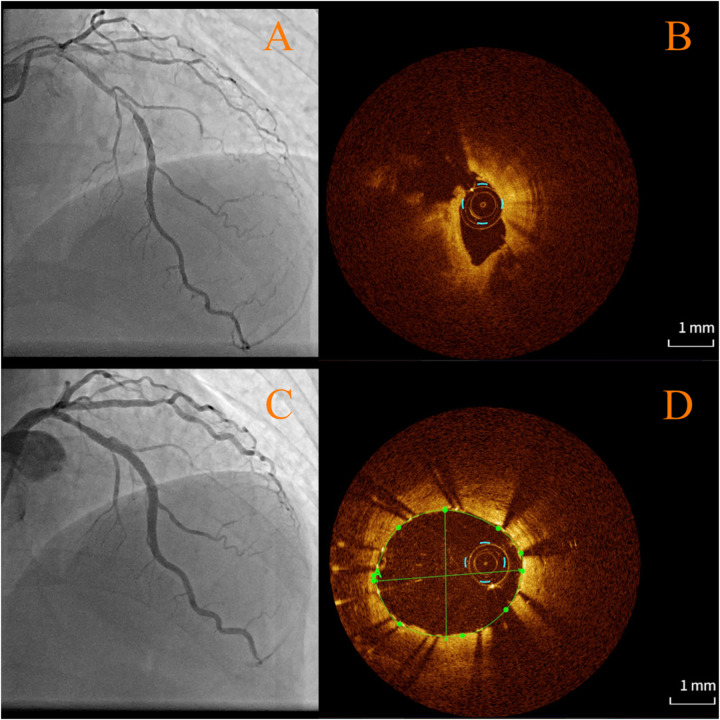

Case summary: A 51-year-old male with immune nephritis, chronic kidney disease (CKD), and poorly controlled hypertension presented with unstable angina. Coronary angiography revealed multivessel disease [70% stenosis in the proximal left anterior descending artery (LAD) and 90% in the posterior descending artery]. Initial treatment included angioplasty with a drug-coated balloon in the posterior descending artery, dual antiplatelet therapy, statins, and prednisone (10 mg/day). Seven months later, after self-reducing GCs to 5 mg/day, he suffered an acute myocardial infarction due to LAD plaque rupture, confirmed by optical coherence tomography (OCT) showing fibrolipid-rich plaques, deep calcifications, and minimal lumen area (0.67 mm2). Emergency stenting was performed to stabilize the patient, with no recurrence at 3-month follow-up.

Discussion: This case underscores the mechanistic duality of GCs. Chronic GC therapy suppresses pro-inflammatory cytokines and macrophage activity, stabilizing plaques by reducing oxidized LDL uptake. However, abrupt tapering may trigger rebound vascular inflammation, destabilizing high-risk lesions. OCT imaging proved critical in identifying vulnerable plaque morphology, emphasizing its role in guiding urgent interventions.